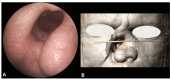

Drug-induced or associated vasculitis is a prevalent form of vasculitis that resembles primary idiopathic antineutrophil cytoplasmic autoantibody (ANCA) vasculitis (AAV). Cocaine is a diffuse psychostimulant drug and levamisole is a synthetic compound used to cut cocaine. Their abuse may result in a spectrum of autoimmune manifestations which could be categorized into three overlapping clinical pictures: cocaine-induced midline destructive lesion (CIMDL), levamisole-adulterated cocaine (LAC) vasculopathy/vasculitis, and cocaine-induced vasculitis (CIV). The mechanisms by which cocaine use leads to disorders resembling AAV are not well understood. Cocaine can cause autoimmune manifestations ranging from localized nasal lesions to systemic diseases, with neutrophils playing a key role through NETosis and ANCA development, which exacerbates immune responses and tissue damage. Diagnosing and treating these conditions becomes challenging when cocaine and levamisole abuse is not suspected, due to the differences and overlaps in clinical, diagnostic, therapeutic, and prognostic aspects compared to primary idiopathic vasculitides.